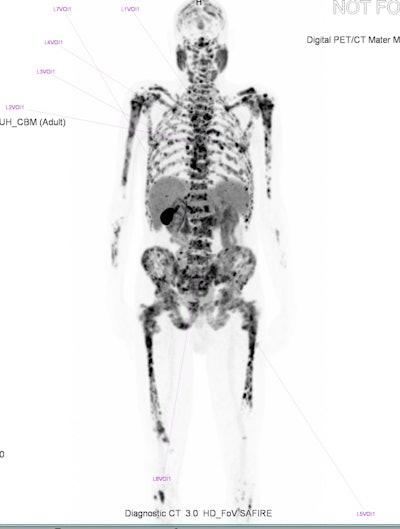

The phenomenon of a “superscan” was first described in 1975 for bone scintigraphy and is considered to be widespread, intense, and largely symmetrical uptake of the osseous radiotracer, typically accompanied by minimal or absent tracer accumulation in the urinary system and soft tissues. This is generally a finding that occurs in technetium-99m hydroxymethylene diphosphonate (Tc-99m HMDP) bone scans, but there have been some reports of the “superscan” appearance with PET/CT, as well as some evidence of it occurring with Ga-68 PSMA PET.

"Superscan" appearance for [F-18]-PSMA-1007.

The first F-18-PSMA-1007 PET study was performed at the Mater in April 2022. The patient had been diagnosed with prostate cancer more than a decade earlier, having multiple nodal, lung, and bone metastases. Despite ongoing treatment with gonadotrophin-releasing hormone agonists, his prostate-specific antigen (PSA) was continually rising.